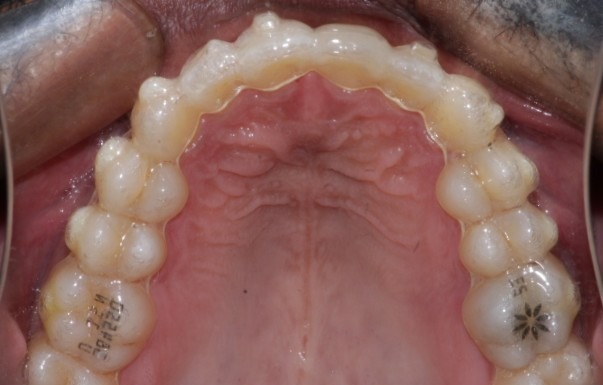

Before: Upper

During The Treatment